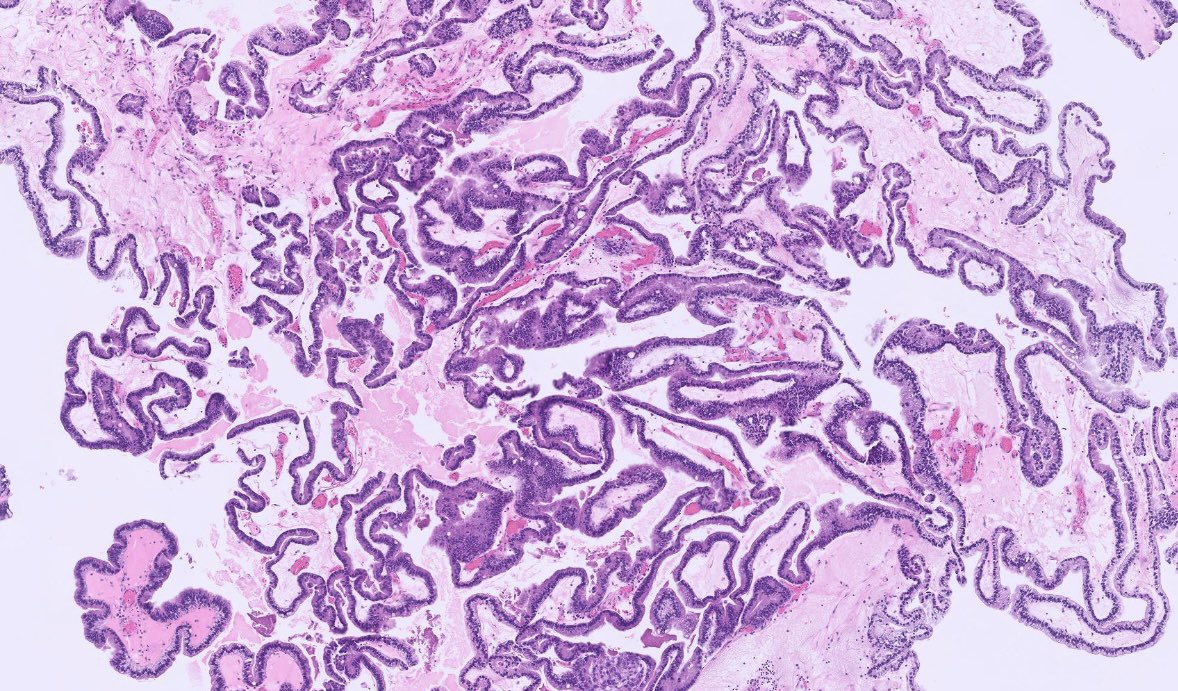

After a long Twitter hiatus because... life... I'm back to bring you this endometrial lesion in a 42 yo woman with abnormal uterine bleeding. Hysteroscopy showed an endometrial polyp in the lower uterine segment #GynePath #GynPath #PathTwitter